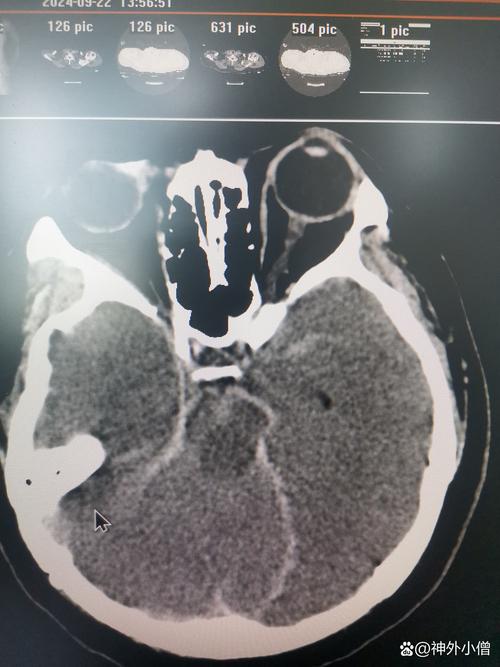

- 脑出血:也叫出血性脑卒中,是因为脑血管破裂,血液流入脑组织,压迫并破坏脑细胞,最常见的原因是高血压导致血管破裂,或血管畸形破裂。

“脆弱的血管” + “抗凝药” = 脑出血风险增加:

- 如果一个房颤患者同时患有高血压,他的脑血管本身就比较脆弱。

- 在这种情况下,即使血压出现一过性的急剧升高(如情绪激动、用力排便等),也可能导致这些脆弱的脑血管破裂出血。

- 由于患者正在服用抗凝药,血液无法正常凝固,出血会持续,甚至加重,从而引发脑出血。

【关键点】:房颤本身不直接导致脑出血,而是房颤患者为了预防脑梗而进行的抗凝治疗,在合并高血压等血管病变的基础上,增加了脑出血的风险,对这类患者的血压控制要求极高。